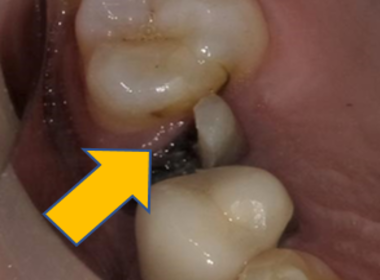

| 0114 #16 右上第一大臼齒 |

![]() |